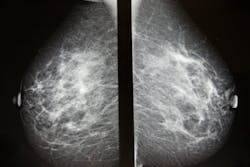

Deep learning model estimates cancer risk from breast density

Researchers led by Prof. Susan M. Astley from the University of Manchester, United Kingdom, recently developed and tested a new deep learning-based model capable of estimating breast density with high precision. Their findings are published in the Journal of Medical Imaging.

Using nearly 160,000 full-field digital mammogram images that were assigned density values on a visual analogue scale by experts (radiologists, advanced practitioner radiographers, and breast physicians) from 39,357 women, the researchers developed a procedure for estimating the density score for each mammogram image. The objective was to take in a mammogram image as input and churn out a density score as output.